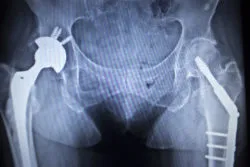

Stryker Metal HipA Wisconsin man has filed a Stryker Accolade hip stem lawsuit, alleging that his failed hip replacement surgery caused severe complications including metal poisoning.

Plaintiff Alan K. underwent hip replacement surgery in July 2007 where he received the Stryker Accolade TMZF Hip Stem and LFIT Anatomic V40 Femoral Head implant.

The Accolade hip implant featuring a titanium stem that is single piece designed to be implanted into the patient’s femur.

The FDA’s recall announcement noted that hip implants are inserted into the thigh bone to provide support to the femoral head in either an initial implantation procedure or a revision procedure.